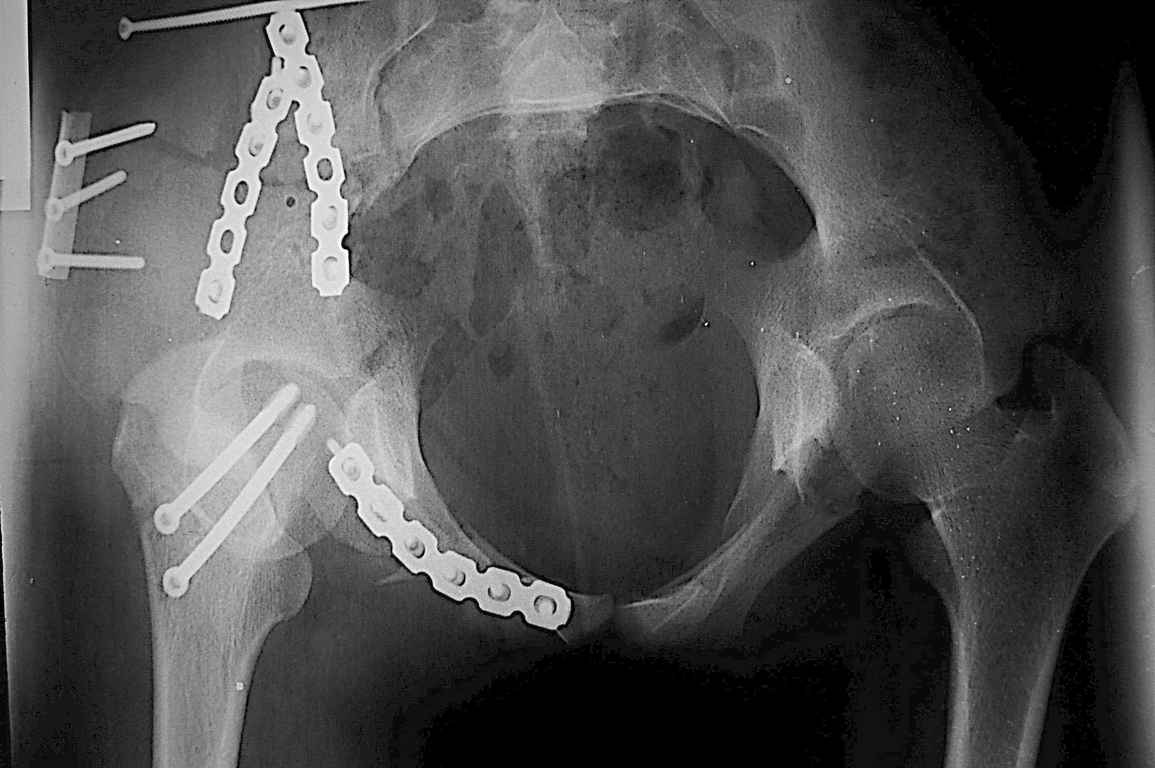

Уважаемый Алексей, на представленных Вами снимках имеется вертикально-нестабильное повреждение тазового кольца без повреждения вертлужной впадины. Учитывая это, а так же растущий возраст ребенка я бы выбрал аппарат внешней фиксации в виде кольцевой опоры, т.к. не смотря на оскольчатый перелом крыла в переднем отделе можно ввести минимум 2 стержня + 1-2 надвертлужно. Этого будет достаточно чтобы "зацепится", выполнить репозицию и дальнейшую фиксацию. Перелом шейки по моему лучше прооперировать 3 канюлированными винтами по АО.

Шейку срочно закрыто винтами.

Таз - подвздошным и падлобковым доступом раздельные рекострукционные пластины 4 штуки. Сплошную пластину как у взрослых нельзя (из-за роста придется доставать)